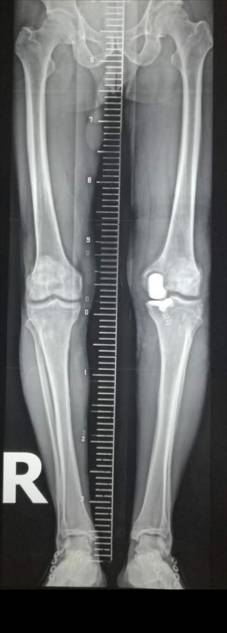

术前术后对比

全膝关节翻修术

全髋关节翻修术